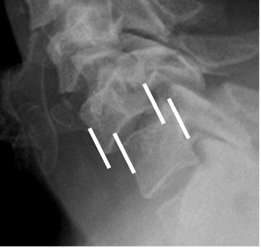

Las anormalidades en la alineación descritas incluyen: interrupción de las líneas intervertebrales anterior y posterior, de la línea espinolaminar, rotación de las apófisis espinosas, ensanchamiento de la distancia interespinosa e interpeduncular. (7, 39). (Fig 164, 165 y 166).

Fig 164. Desalineación.

Rx lateral. Anterolistesis post-traumática, con interrupción en las líneas intervertebral anterior y posterior.